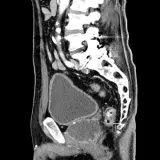

Over 2,100 interactive radiology cases, curated by radiologists for your level of training. Scroll, window, and view cases full screen — just like on PACS. Click linked findings in each writeup to jump straight to them on the image. Cases include sample reports, a focused discussion section, original illustrations, and videos.

Casos totalmente interactivos con las herramientas que esperaría de un PACS: scroll, ventana, zoom, pan, mediciones, ROI y modo de pantalla completa.

• Anotaciones enlazadas

Anotaciones extensas resaltan los hallazgos clave directamente sobre los casos. Haga clic en los hallazgos enlazados dentro de la descripción del caso para saltar a su ubicación exacta en el estudio.